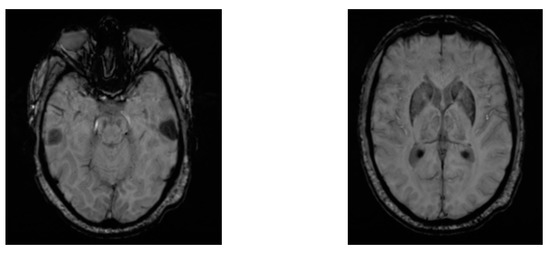

Zhang et al. proposed a novel approach for screening de novo PD patients at an accuracy of 76.46% using deep neural networks applied on 102 two-view MRI data: AXI and SAG data [33]. The two-view data were preprocessed using image augmentation techniques based on Wasserstein Generative Adversarial Networks (WGANs). Further, two ResNeXt networks were applied to the two-view data jointly, and the hidden layer outputs from the two ResNeXt networks were conjugated in a vector and fed into a Softmax classification layer. Figure 7 shows two views of the axial susceptibility weighted imaging (SWI) MRI images for a PD patient (age: 60 years, gender: male).

Figure 7.

Two views of AXI SWI MRI images for a male PD patient.